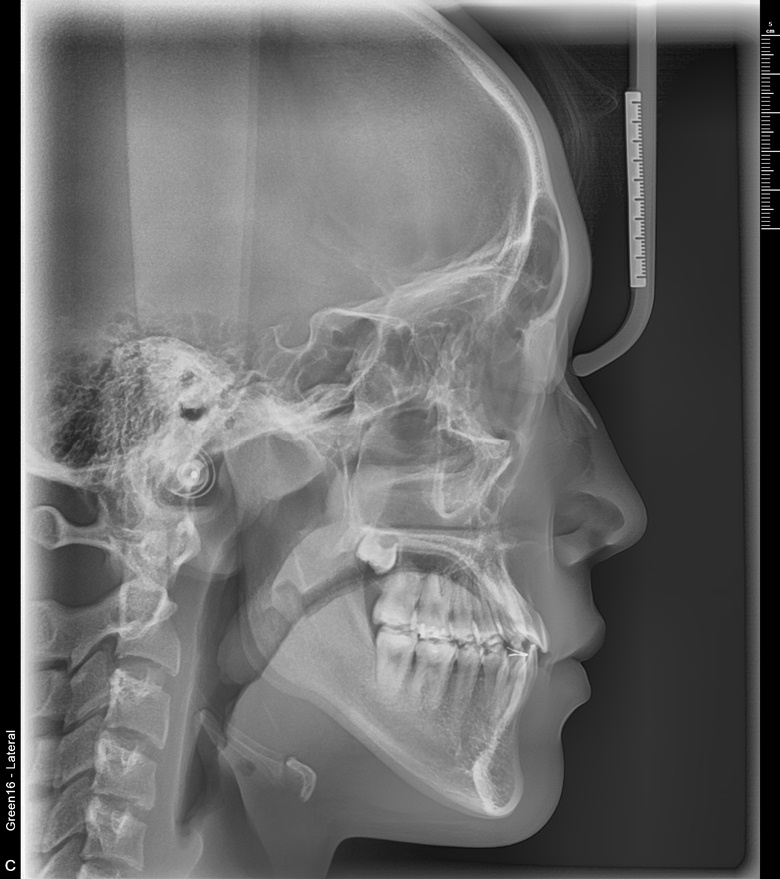

치료 후 사진입니다.